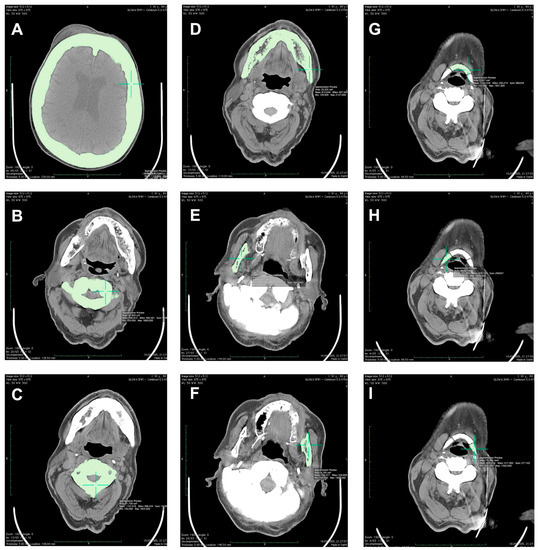

| Cranium | |||||

| 50% of cranium height | - | - | - | - | 2.111 |

| Mandibular body | - | - | - | - | 1.812 |

| Right ramus | - | - | - | - | 1.678 |

| Left ramus | - | - | - | - | 1.757 |

| Hyoid | |||||

| Middle part | - | - | - | - | 2.135 |

| Right part | - | - | - | - | 1.731 |

| Left part | - | - | - | - | 1.840 |